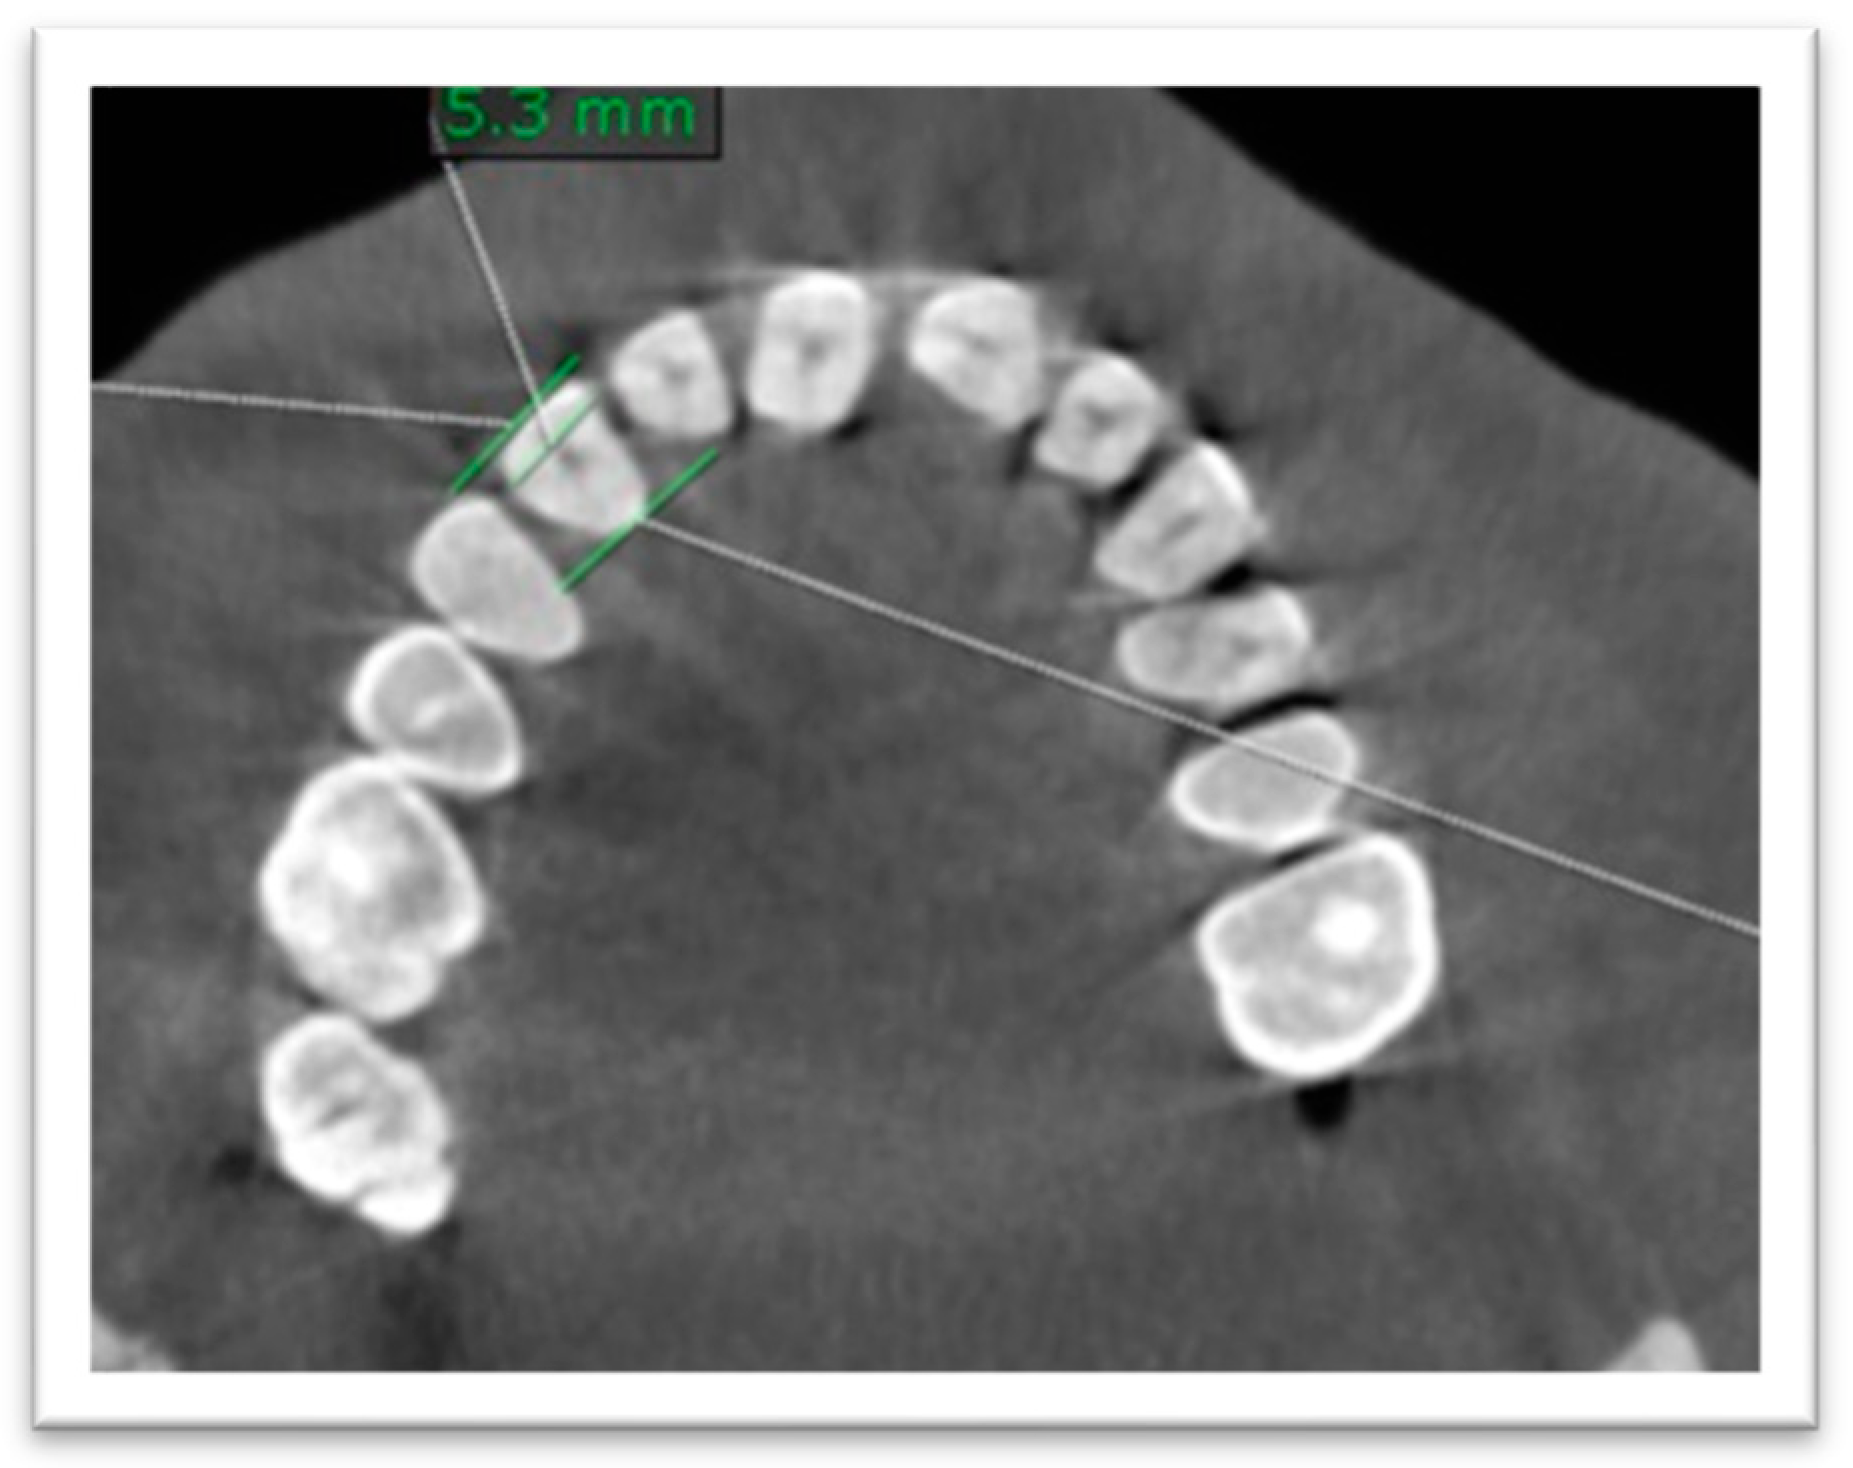

- (3)

- Mesiodistal diameter was measured at the CEJ level on the axial plane (Figure 3).